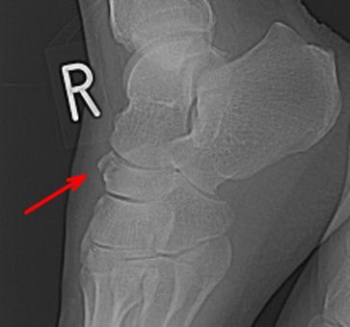

舟状骨骨折

舟状骨骨折の分類

①舟状骨体部骨折

②舟状骨粗面骨折

舟状骨骨折の発生機序

介達外力によるによる発生頻度が高い。

骨体部の骨折は高所より墜落して足部アーチが圧平され、アーチの最高部にある舟状骨が距骨骨頭と喫状骨によって強く圧迫されて骨折する。

背側の骨片は転位し脱臼することが多い。

舟状骨粗面の骨折は、足部の外転により後脛骨筋の牽引力による剥離骨折を起こす。

直達外力によって、上方または下内方の粗面が骨折することがある。